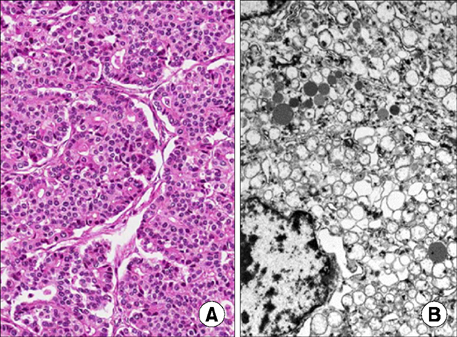

The patient started a standard diet 9 days postoperatively and was discharged the following day. Pathological diagnosis of the tumor determined a mitotic count of 50 cells/10 HPF; 30% of the tissue was necrotic, and the tumor cells were positive for chromogranin A and synaptophysin, which supported the final diagnosis. Ki-67 proliferative staining was positive in 80% of cells, and the tumor cells were positive for beta-catenin, CD10, E-cadherin, and cytokeratin (

Fig. 2,

3). The final pathological diagnosis was mixed acinar-endocrine carcinoma. The patient is currently undergoing adjuvant chemotherapy with cisplatin, etoposide, and cyclophosphamide in our pediatrics department; the regimen of chemotherapeutic agents used was based on the standard regimen used to treat pancreatoblastoma.

Fig. 3Immunochemical staining of the biopsy specimen. Chromogranin A (×100) (A), synaptophysin (×40) (B), and E-cadherin (×40) (D) were focally positive, whereas Ki-67 (×40) (C) was positive in 80% of the specimen.